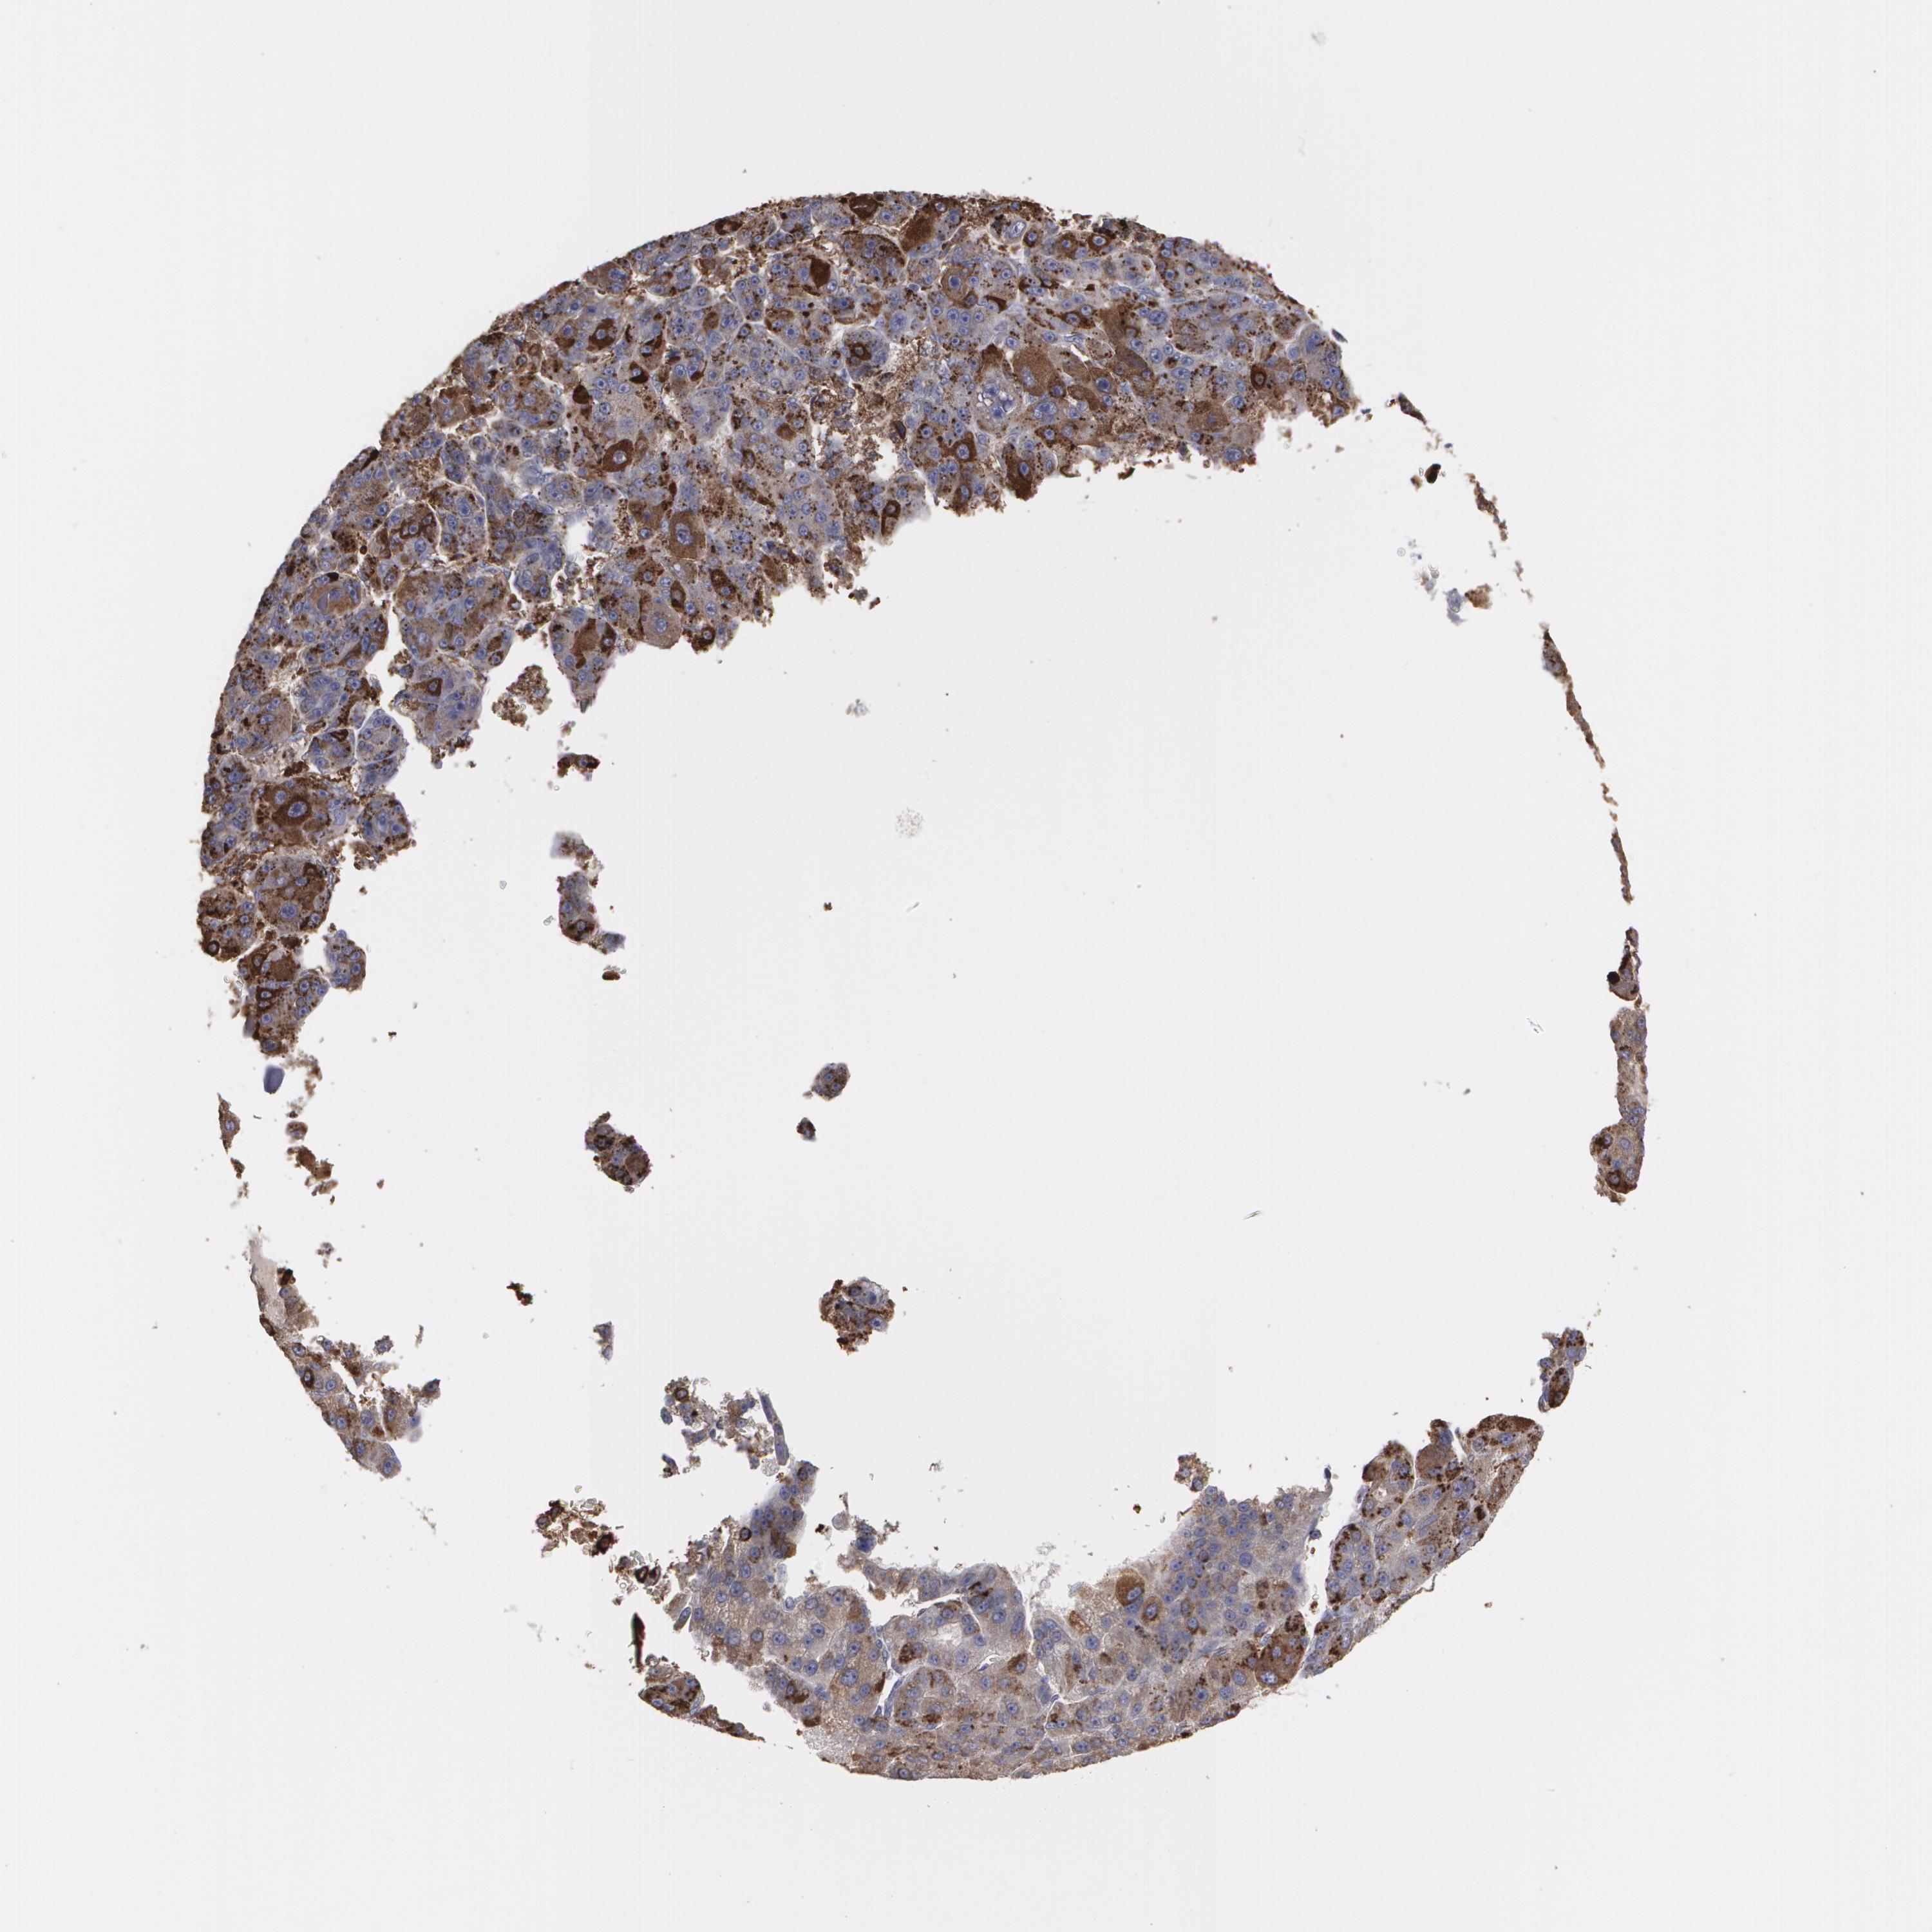

LIVER CANCER - Protein expressioni

A mouse-over function shows sample information and annotation data. Click on an image to view it in a full screen mode. Samples can be filtered based on level of antibody staining by selecting one or several of the following categories: high, medium, low and not detected. The assay and annotation is described here.

Note that samples used for immunohistochemistry by the Human Protein Atlas do not correspond to samples in the TCGA dataset.

Antibody stainingi

Antibody staining in the annotated cell types in the current human tissue is reported as not detected, low, medium, or high, based on conventional immunohistochemistry profiling in selected tissues. This score is based on the combination of the staining intensity and fraction of stained cells.

Each image is clickable and will lead to virtual microscopy that enables deeper exploration of all samples and also displays staining intensity scores, fraction scores and subcellular localization as well as patient and tissue information for each sample.

Antibody HPA001536

Antibody CAB035996

Staining

High

Medium

Low

Not detected

Intensity

Strong

Moderate

Weak

Negative

Quantity

>75%

75%-25%

<25%

None

Location

Nuclear

Cytoplasmic/membranous

Cytoplasmic/membranous,nuclear

Cholangiocarcinoma

Carcinoma, Hepatocellular, NOS